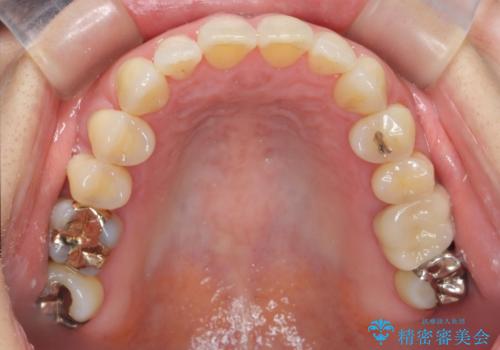

- 食いしばりがひどくてセラミックの被せ物が欠けたとの事で来院。

欠けたセラミックを新しいセラミックに変えた後、今後欠けたり割れたりしないように

ナイトガード(自費)を作製しました。

保険のナイトガードに比べて自費のナイトガードは割れる心配がないです。

また噛み合わせの歯と調整をして全体に均一に当たるように調整を行うので噛んだとき力が全体的に分散して歯の負担も減ります。